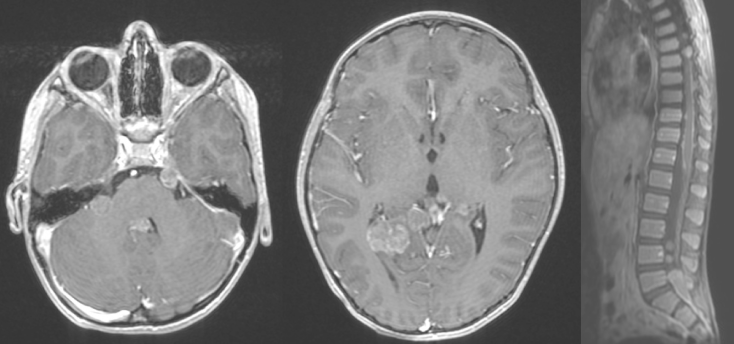

enfant de 11 mois, lésion de l’angle ponto-cérébelleux révélé par vomissements et hypotonie - la présence de métastases névraxiques dès le diagnostic dans plus de la moitié des cas ; la dissémination est soit radiologique soit dépistée sur l’étude du LCS.

enfant de 7 ans, multiples lésions cranio-spinales révélé par altération de l’état général et rétention urinaire - parfois une tumeur multi-loculaire

enfant d’un mois, ATRT bifocale épidurale lombo-sacrée et intra-durale dans le quatrième ventricule, révélée en même temps par signes d’engagement et une paraplégie.